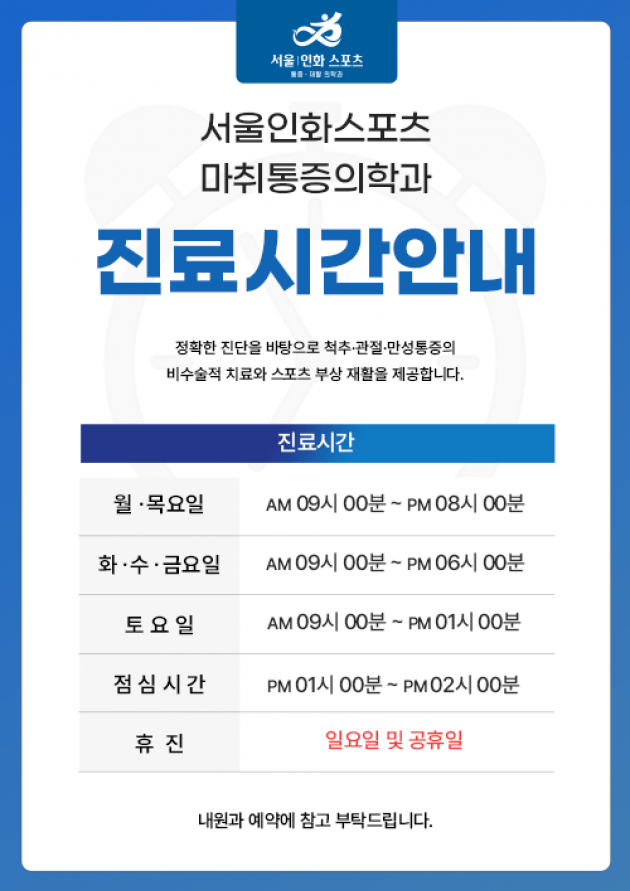

월•목 오후 8시까지 야간진료

월•목 오후 8시까지 야간진료